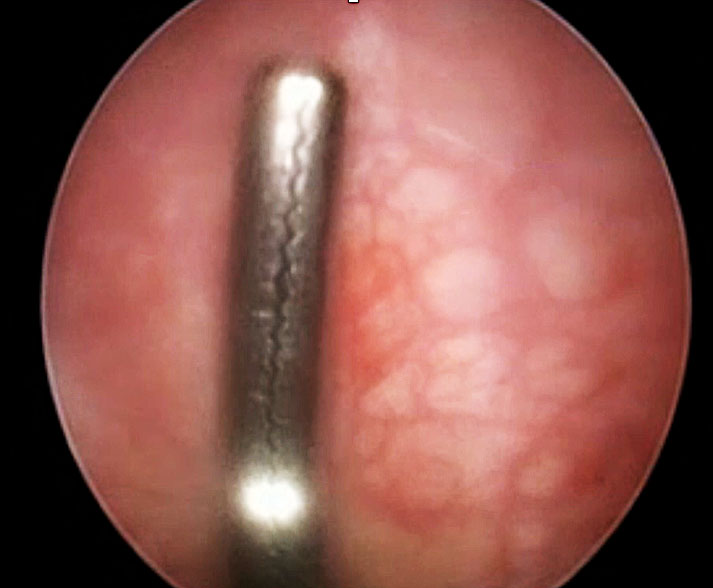

Vessel injuries

Injury to the inferior epigastric artery can occur by ancillary side trocars (Figure 15a). If bleeding is acute, a Foley catheter can be passed through the trocar, the bulb distended to provide tamponade, and the trocar then removed (Figure 15b). Under visualization, bipolar cauterization from another port can be used for coagulation, while applying external pressure with a finger on the abdominal wall adjacent to the trocar site (Figure 15c). A through-and-through suture placed on either side of the port site, with a gauze pad on the skin surface, can help control bleeding. The trocar should then be reinserted at a different site to continue the procedure.

(a) |

(b) |

(c) |

15

(a) Left inferior epigastric artery. (b) Foley-bulb tamponade. (c) Bipolar seal bleed on trocar entry.